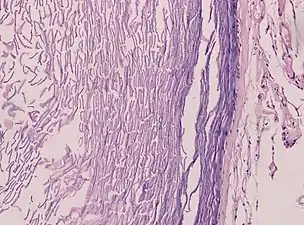

An epidermoid cyst or epidermal inclusion cyst[1] is a benign cyst usually found on the skin. The cyst develops out of ectodermal tissue. Histologically, it is made of a thin layer of squamous epithelium.

Epidermoid cysts are usually diagnosed when a person notices a bump on their skin and seeks medical attention. The definitive diagnosis is made after excision by a pathologist based on microscopic appearance of a cystic lesion lined by cornified epithelium containing lamellated keratin without calcifications. They can also be seen as isointense lesions on MRI or hyperintensities on FLAIR.